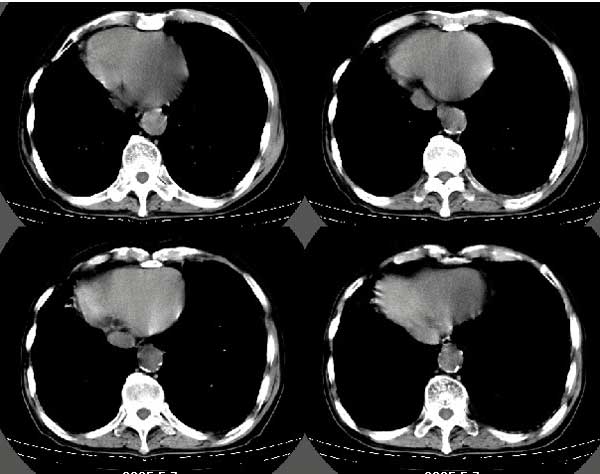

以下是引用扬仪在2005-5-12 20:46:40的发言:[br]右肺呈术后改变;双侧肺野散在分布斑片状、点状高密度病灶,(似可见“树芽征”);左上尖后段见斑团状高密度病灶(2个层面?),边缘毛糙,段性分布,与斜裂相邻,临近胸膜粘连;增强示病灶边缘强化,内呈水样密度;心影、纵隔右移,内可见4r淋巴结肿大。[br]意见:1、双肺继发性肺结核,左上为干酪病灶;[br] 2、矽肺合并感染;[br] 3、建议抗痨+抗炎。 [br]愚人之见,请高人指教!